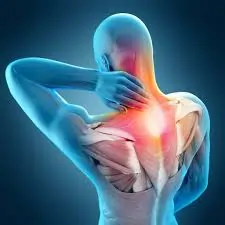

મોબિલિટી એક્સરસાઇઝ (Mobility exercises) આધુનિક ફિટનેસ અને રિહેબિલિટેશન (પુનર્વસન) દિનચર્યાઓનો એક આવશ્યક ભાગ બની ગઈ છે. ભલે તમે રમતવીર હોવ, ફિટનેસના શોખીન હોવ અથવા બેઠાડુ જીવનશૈલીને કારણે જડતાનો સામનો કરી રહ્યાં હોવ, તમારી ગતિશીલતા (mobility) સુધારવાથી તમારા જીવનની એકંદર ગુણવત્તામાં નોંધપાત્ર વધારો થઈ શકે છે. સાચા અર્થમાં ફક્ત સ્ટ્રેચિંગ કરવા કરતાં અલગ, મોબિલિટી એક્સરસાઇઝ સાંધાની…